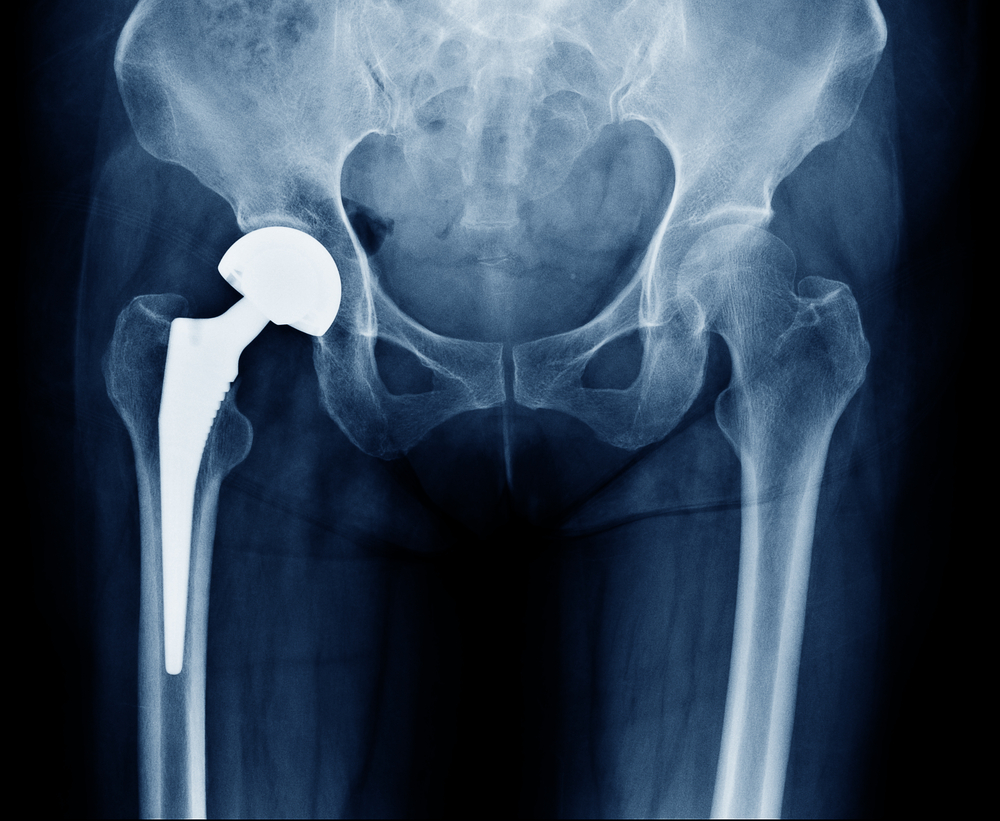

Advancements in hardware

One reason patients delayed hip replacements was concern about implant longevity — how long a replacement would last without needing a second procedure.

The good news is that surgical prostheses are lasting longer than ever, thanks to technological advancements.

A study by the National Center for Biotechnology Information reported significant advances in the last few years in the wear resistance of materials and the biocompatibility and bone ingrowth capability of the biomaterials.

- Improved precision in placing components as a result of intra-operative X-ray technology.